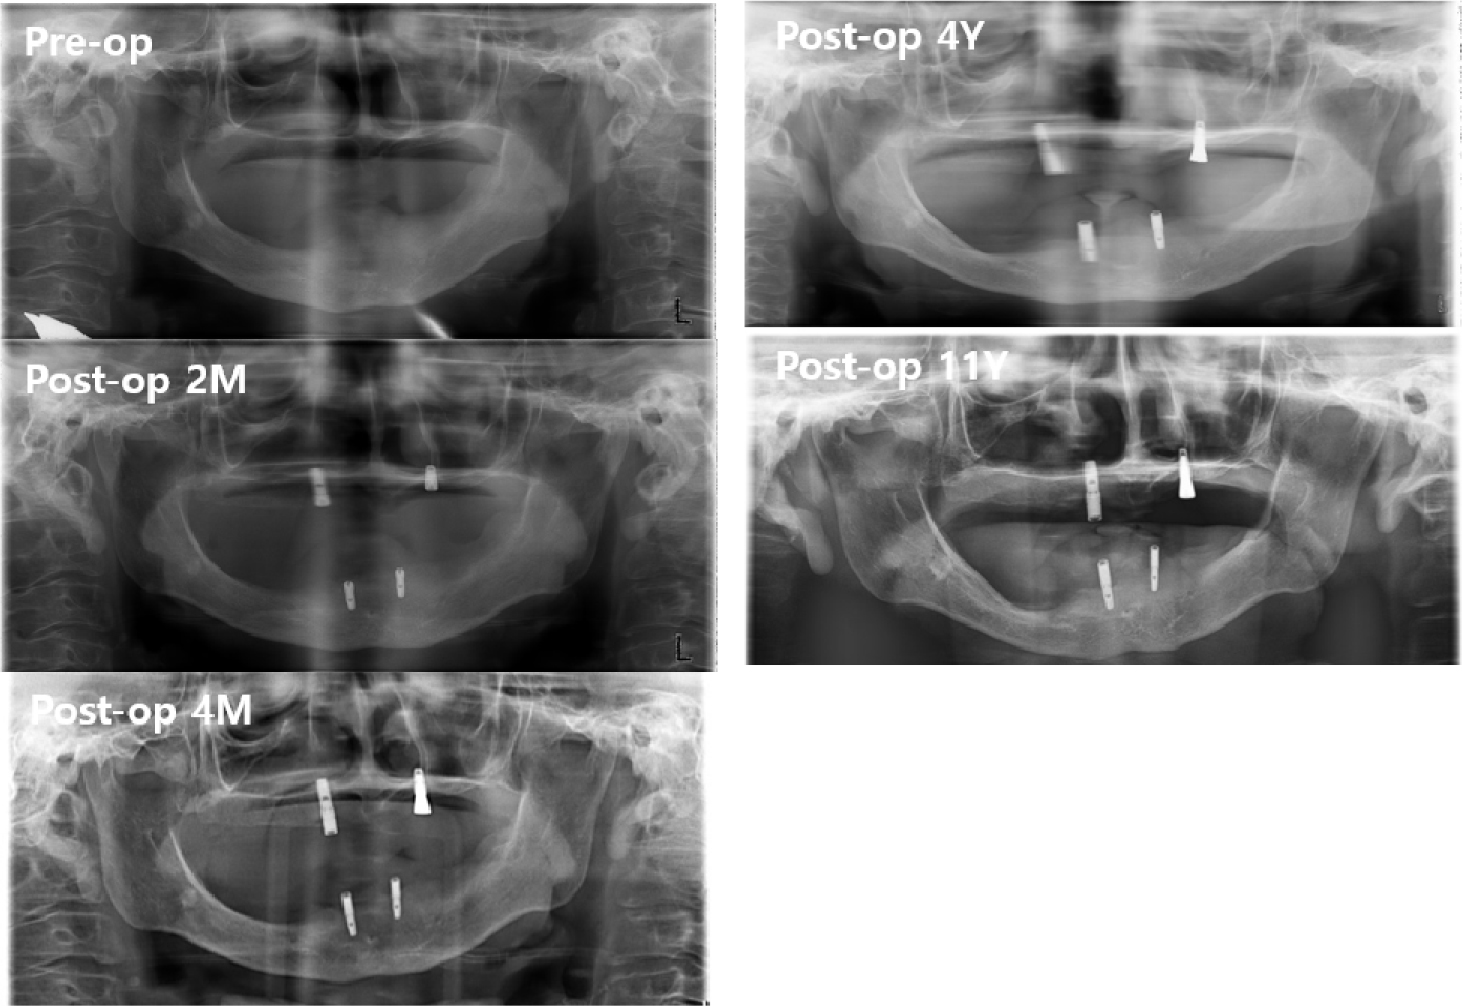

Postoperatively, the maximum mouth opening was increased from 12 to 35 mm, and the oral commissure was enlarged. After 2 months of recovery, temporary complete upper and lower dentures were delivered to the patient (Fig. 6). On January 19, 2011, two implants were placed in each arch under general anesthesia (Fig. 7). A panoramic radiograph revealed four implants (Fig. 8). At the Department of Prosthodontics, magnet-attached overdentures were fabricated and delivered 6 months after implant installation (Fig. 9). Vestibuloplasty creates a larger surface area for better denture adaptation. The patient was followed-up for 11 years without any complications (Fig. 10).

Compared with ball and attachments, magnet attachment has the least amount of strain regardless of implant number and distribution.16 However, magnets require encapsulation within an inert alloy because of poor corrosion resistance within oral fluids.15 In the 11-year follow-up, the upper and lower implant-supported overdentures were in good condition. The patient did not experience any pain around the implants. Implant mobility was not observed. The maximum mouth opening was reduced by approximately 5 mm, which may be due to inevitable scar contracture.